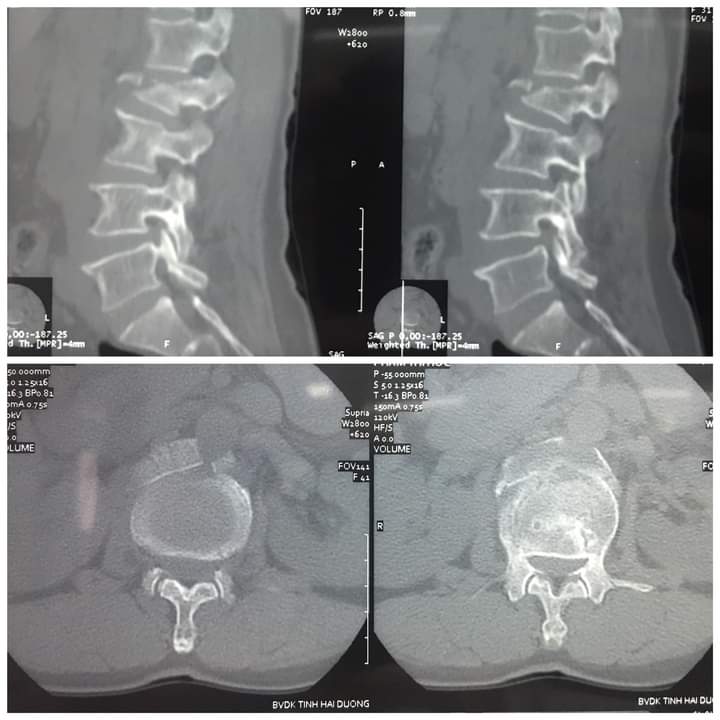

Anh Q vào viện do ngã cây vải đau nhiều cột sống thắt lưng, liệt hoàn toàn 2 chi dưới đã được các bác sĩ khoa cấp cứu BVĐK Tỉnh Hải Dương khám, cố định cột sống, chụp chiếu chẩn đoán CTCS gãy D12 L1 mất vững Frankel A , a đã được các bác sĩ hội chẩn và được các bác sĩ khoa ngoại 2 Phẫu thuật cấp cứu làm vững cột sống, giải ép tủy, khâu phục hồi màng tủy. Sau 10 ngày điều trị hiện tại sức khỏe của anh Q ổn định và được tập phục hồi chức năng, tuy đã phẫu thuật nhưng do tổn thương của anh Q phức tạp tổn thương tủy sống nên sự hồi phục vận động và cảm giác của a Q rất chậm và cần phải có một thời gian rất dài.